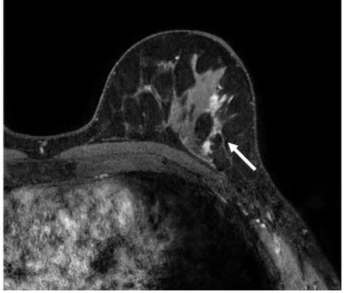

One of the recommendations from the European Society of Breast Imaging (EUSOBI) is annual breast MRI exams starting at 25 years of age for women deemed to be at high risk for breast cancer.

In a new literature review, researchers noted key findings on the use of breast MRI in facilitating breast cancer detection for women with dense breasts and others at high-risk for breast cancer.

In a study of nearly 2,500 women with BRCA1 or BRCA2 sequence variations, researchers found that MRI surveillance led to a 3.2 percent breast cancer mortality risk at 20 years in contrast to a 14.9 percent mortality risk for those who did not have MRI surveillance.